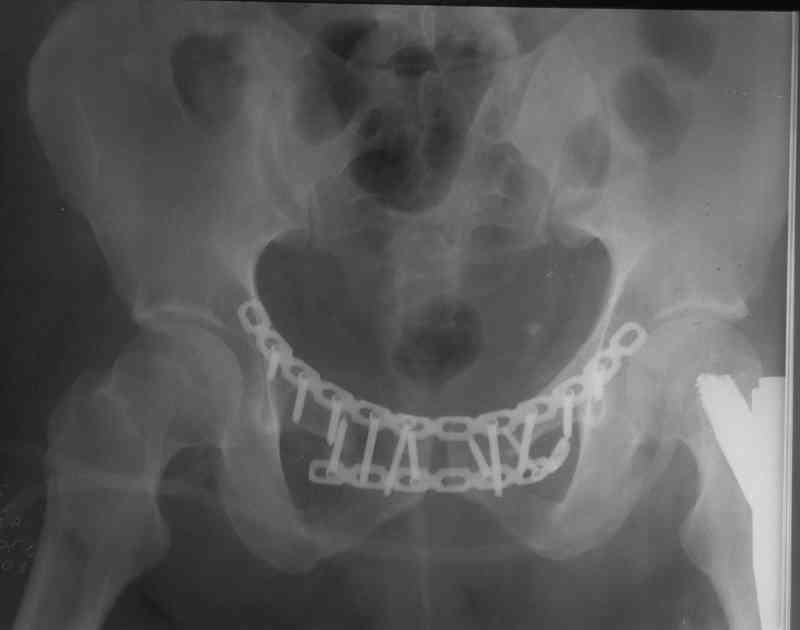

Вчера прооперировал больного.

Попытка низвести половину таза на тракционном столе ( скелетное вытяжение за бедро) безуспешная.

из переднего доступа добрался до правого КП сочленения , все запаяно костью, с помощью 2 шанцев винтов в крестец и подвздошную кость и элеватора репозиция, контроль ЭОП

и двумя пластинами фиксация.

Спереди, аппарат как рекомендовал Джолдас.

Снимки плохого качества( очень темные) завтра переделают и пришлю на конференцию.

На мой взгляд, смещение устранено и фиксация выглядит вполне анатомичной.

В приложении послеоперационные картинки.

Всего доброго,

Спасибо всем принявшим участие в обсуждении,

Чекашкин Е.И.